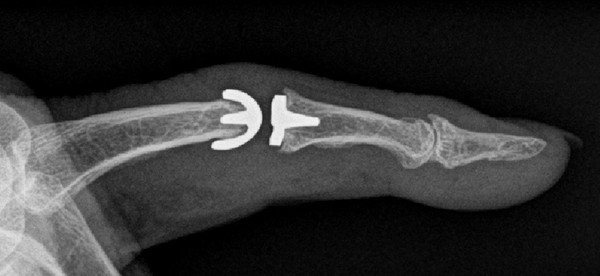

Die Fingergrund- und -mittelgelenke stellen wichtige Elemente in der Gesamtbeweglichkeit eines Fingers dar. Wenn immer möglich bevorzugen wir deshalb einen bewegungserhaltenden Eingriff. Dabei haben sich Silikonkunstgelenke als präferierte Wahl herausgestellt – sie bewähren sich seit über fünfzig Jahren sehr gut. Mit dem Kunstgelenk bleibt eine gewisse Beweglichkeit erhalten, was zusammen mit der Schmerzbefreiung eine erhebliche Verbesserung der Lebensqualität für den Patienten bedeutet.

Neuentwicklungen als Oberflächenersatz (ähnlich einem Kunstgelenk für ein Knie) zeigen ebenfalls vielversprechende Resultate mit einer gegenüber Silikon verbesserten Stabilität. Deren Einsatz ist jedoch nur bei guter Knochenqualität möglich und muss im Einzelfall besprochen werden.

eines anatomischen Oberflächenersatzes (rechts)